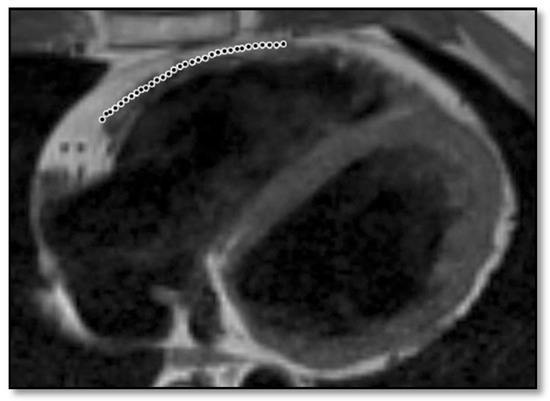

- Thinning of the RV wallThis is a component that was not included in the Task Force Criteria for the diagnosis of ARVC [12,45]. This is because the reports of different authors were not consistent with regards to the thinning or thickening of the ventricular wall. Therefore, thinning of the wall is considered pathological only when associated with contraction abnormalities at the same level [48] (Figure 6).